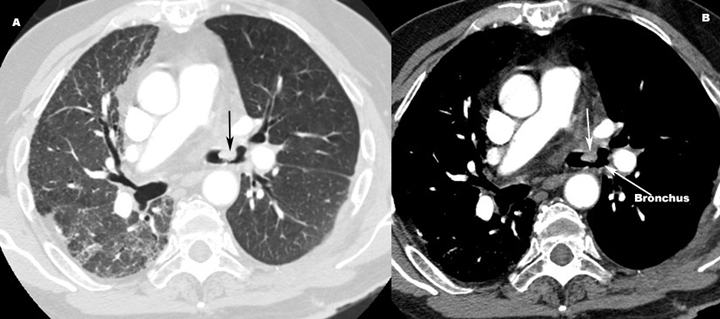

Endobronchial Mucus Plug